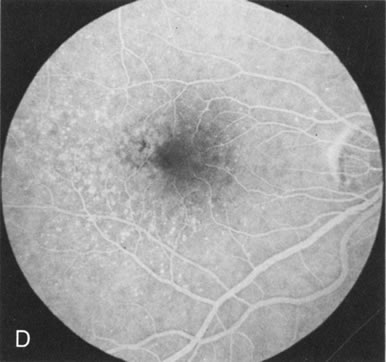

In Stargardt's disease, thes most common hereditary macular dystrophy, FA has a variety of functions. In the mildest fundus presentation, with visual symptoms and visual function out of proportion to the observed maculopathy, FA can confirm or even make the diagnosis and can avoid a mistaken diagnosis of malingering, hysteria, or central nervous system disease (Fig. 9A and B). When a maculopathy is present without surrounding parafoval flecks, FA may show patchy areas of transmission hyperfluorescence in the posterior pole, indicating a more diffuse involvement (Fig. 9C and D).

Fig. 9. Stargardt's disease–fundus flavimaculatus. The mild maculopathy (without parafoveal flecks) (A) is confirmed by the angiogram (B). The relative absence of the underlying choroidal flush, resulting in an easier visualization of the overlying retinal capillary circulation, has been referred to as the “silent” or “dark” choroid, and is considered a common finding in this disease. The diagnosis is confirmed in an individual with a pigmentary maculopathy without flecks (C). Here the angiogram demonstrates widespread transmission hyperfluorescence and a “silent” or “dark” peripapillary area (D). When the posterior pole shows multiple yellowish-white flecks (E), the angiographic findings do not necessarily correspond to the flecks (F). It should also be noted that despite the widespread abnormalities, the background choroidal fluorescence is normal.

In a large majority of patients (86% in one study),20 there is an absence or decrease in the background choroidal fluorescence (which is referred to as the “silent” or “dark” choroid) (see Fig. 9B). This warrants special attention because it occurs so frequently, is rarely found in other retinal disorders,21 and may be related to histopathology that shows an increase in lipofuscin in the RPE.22